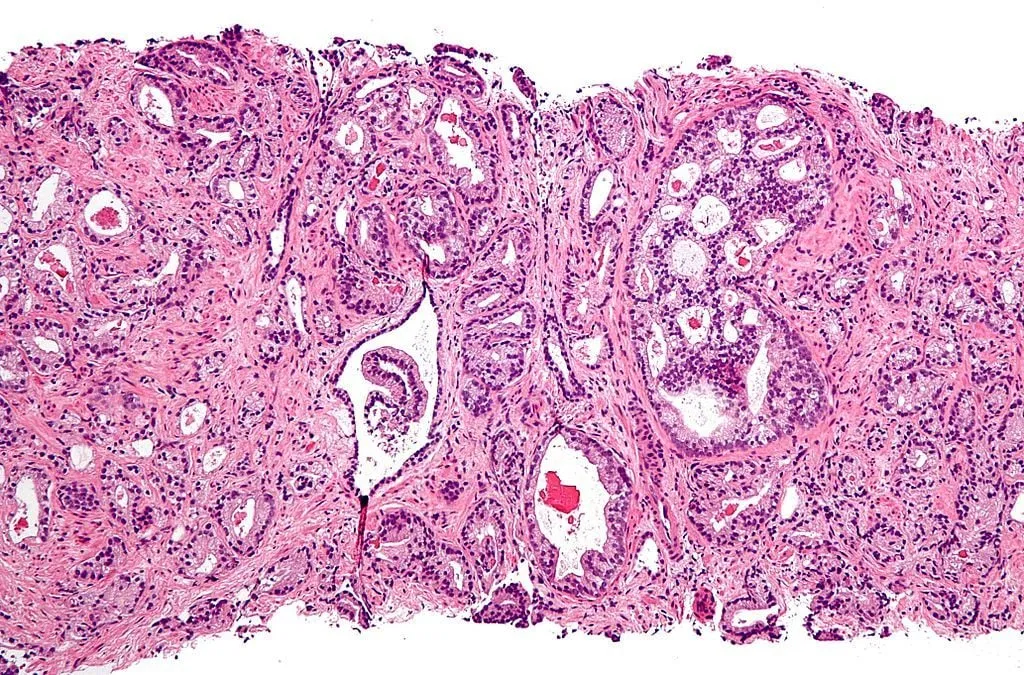

Photo : micrographie montrant un adénocarcinome acineux de la prostate (la forme la plus courante de cancer de la prostate)